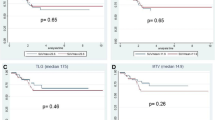

The AUCs for early RI in identifying non-cPR patients according to the ypTNM classification and TRG score were, respectively, 0.74 (95 % CI 0.61 – 0.87) and 0.75 (95 % CI 0.62 – 0.88); the optimal cut-off was a reduction of 61.2 % (83.1 % sensitivity and 65.0 % specificity in identifying ypT1–4 N0–2 patients; 85.4 % sensitivity and 65.2 % specificity in identifying TRG2–5 patients; Fig. 4). Among the 27 patients with an early RI lower than −61.2 %, 12 (44.4 %) were classified as TRG2–5. In contrast, among the remaining 78 patients with an early RI higher than −61.2 %, 70 (89.7 %) were TRG2–5 (positive predictive value, PPV, 89.7 % in identifying non-cPR patients and negative predictive value, NPV, 55.6 % in identifying cPR patients). The relationship between the early RI cut-off and histopathological response (TRG1 vs. TRG2–5) is presented in Table 4. The AUCs for late RI in identifying non-cPR patients were, respectively, 0.64 (95 % CI 0.49 – 0.79) for ypT1–4 N0–2 patients and 0.64 (95 % CI 0.50 – 0.78) for TRG2–5 patients; these values were considered not sufficiently accurate to establish an optimal cut-off (Fig. 4).

ROC curve for early and late RIs. The curve shows the accuracy of using early RI (blue line) for predicting complete pathological response (non-cPR vs. cPR) from the TRG score (AUC 0.75, 95 % CI 0.62 – 0.88): the optimal cut-off value was a SUVmax reduction of 61.2 %). The AUC of late RI (green line) is not sufficiently accurate to establish the optimal cut-off (AUC 0.64, 95 % CI 0.50 – 078)